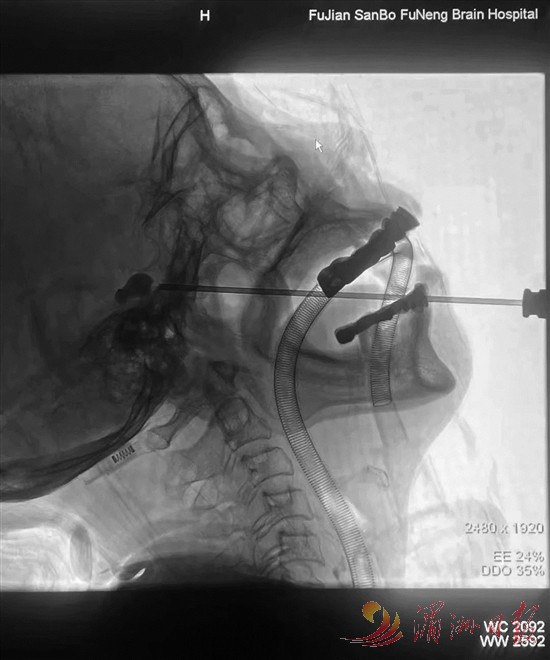

三叉神经痛被称为“天下第一痛”,患者常因剧痛不敢进食、洗脸,甚至丧失生活信心。医院在省内率先引入“三叉神经半月节球囊压迫”技术,以微创方式替代传统的开颅手术破解难题:手术仅需10余分钟,在患者嘴角穿刺针眼大小的创口,用球囊精准压迫痛觉神经,术后即刻缓解疼痛。一位饱受疼痛折磨十余年的李阿姨,术后摸着面颊哽咽道:“张主任的‘神针’,让我重获新生”。